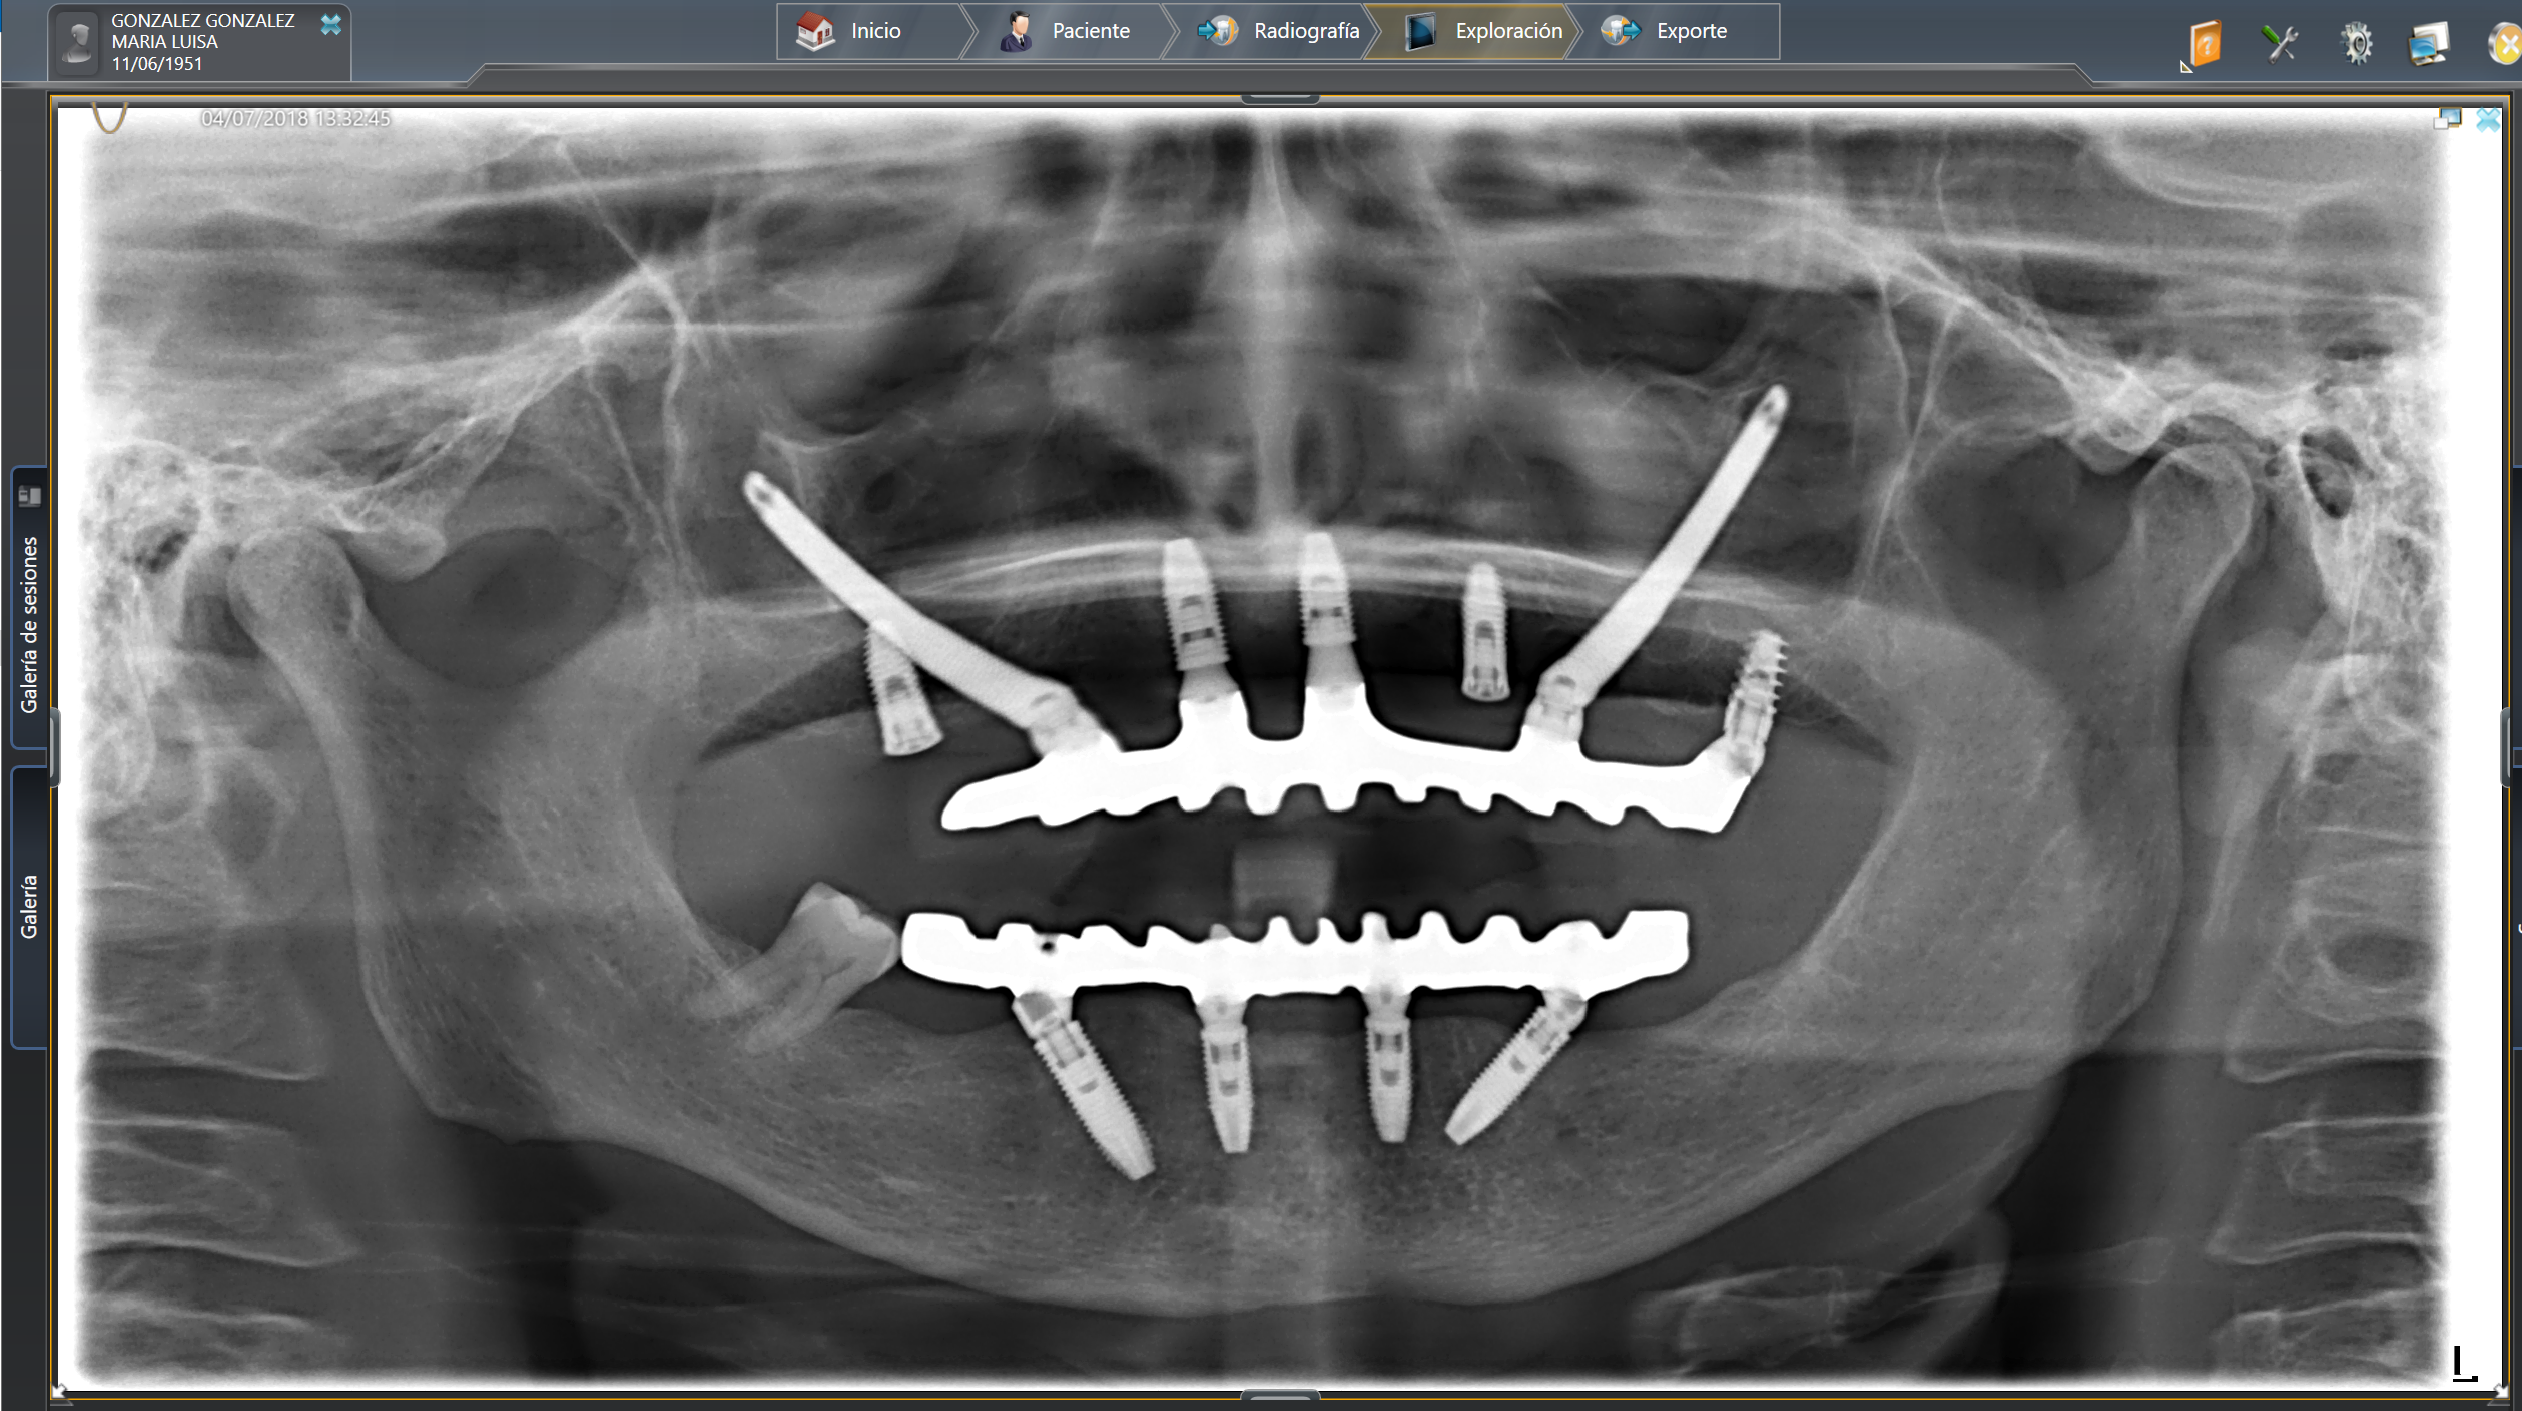

AllOn4

AllOn4 (All on Four) é uma técnica cirúrgica e protésica de implantologia e reabilitação oral, realizada pelo Dr. Mariano Arranz Rodríguez. Trata-se da colocação de 4 implantes, sobre os quais se fixam próteses com 12 ou 14 dentes.